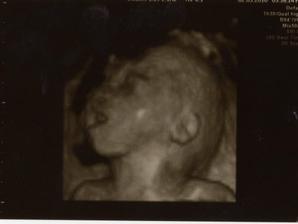

2.3.2010, 22+4tt - 3D UTZ